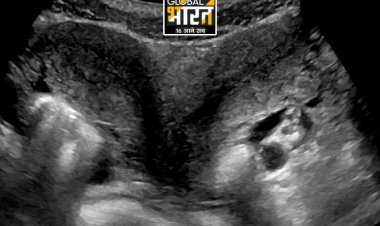

नई दिल्ली: मध्य प्रदेश के छतरपुर जिले से एक बेहद दुखद और चौंकाने वाली घटना सामने आई है. यहां मात्र 20 वर्षीय एक युवक की अचानक मौत हो गई, जिसे स्थानीय लोग साइलेंट हार्ट अटैक बता रहे हैं. ऐसी घटनाएं दिल दहला देने वाली होती हैं, खासकर इतनी कम उम्र में.

शुक्रवार सुबह करीब 10 बजे घर पर नाश्ता कर रहे युवक को अचानक सीने और पेट में तेज दर्द हुआ. हालत बिगड़ती देख परिवार ने तुरंत उसे जिला अस्पताल पहुंचाने की कोशिश की, लेकिन रास्ते में ही उसकी सांसें थम गईं. अस्पताल पहुंचने पर डॉक्टरों ने उसे मृत घोषित कर दिया.

इस अचानक मौत से परिवार, पड़ोसी, स्थानीय व्यापारी और जैन समाज में गहरा शोक व्याप्त है. कई लोग इसे साइलेंट अटैक मान रहे हैं. कुछ परिजनों और स्थानीय लोगों का कहना है कि कोविड वैक्सीन के संभावित साइड इफेक्ट्स के कारण हाल के समय में युवाओं में ऐसी घटनाएं बढ़ रही हैं, इसलिए मौत के सही कारण की गहन जांच होनी चाहिए.